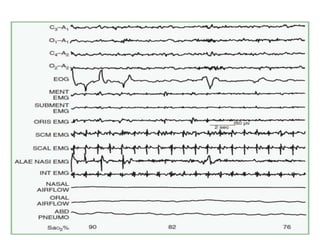

Laboratory Assessment of

Sleep Disorders

• The two most important laboratory tests for

diagnosis of sleep disturbance are PSG and the

MSLT

• overnight PSG study is the single most

important laboratory test for the diagnosis

and treatment of patients with sleep disorders

• EEG, EMG, EOG, ECG, SaO2, Nasal and oral

airflow, Respiratory effort (chest and

abdomen)